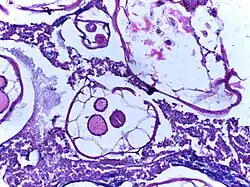

_(15806559973).jpg)

.jpg)

If complications of helminthiasis, such as intestinal obstruction occur, emergency surgery may be required.[9][57] Patients who require non-emergency surgery, for instance for removal of worms from the biliary tree, can be pre-treated with the anthelmintic drug albendazole.[9]